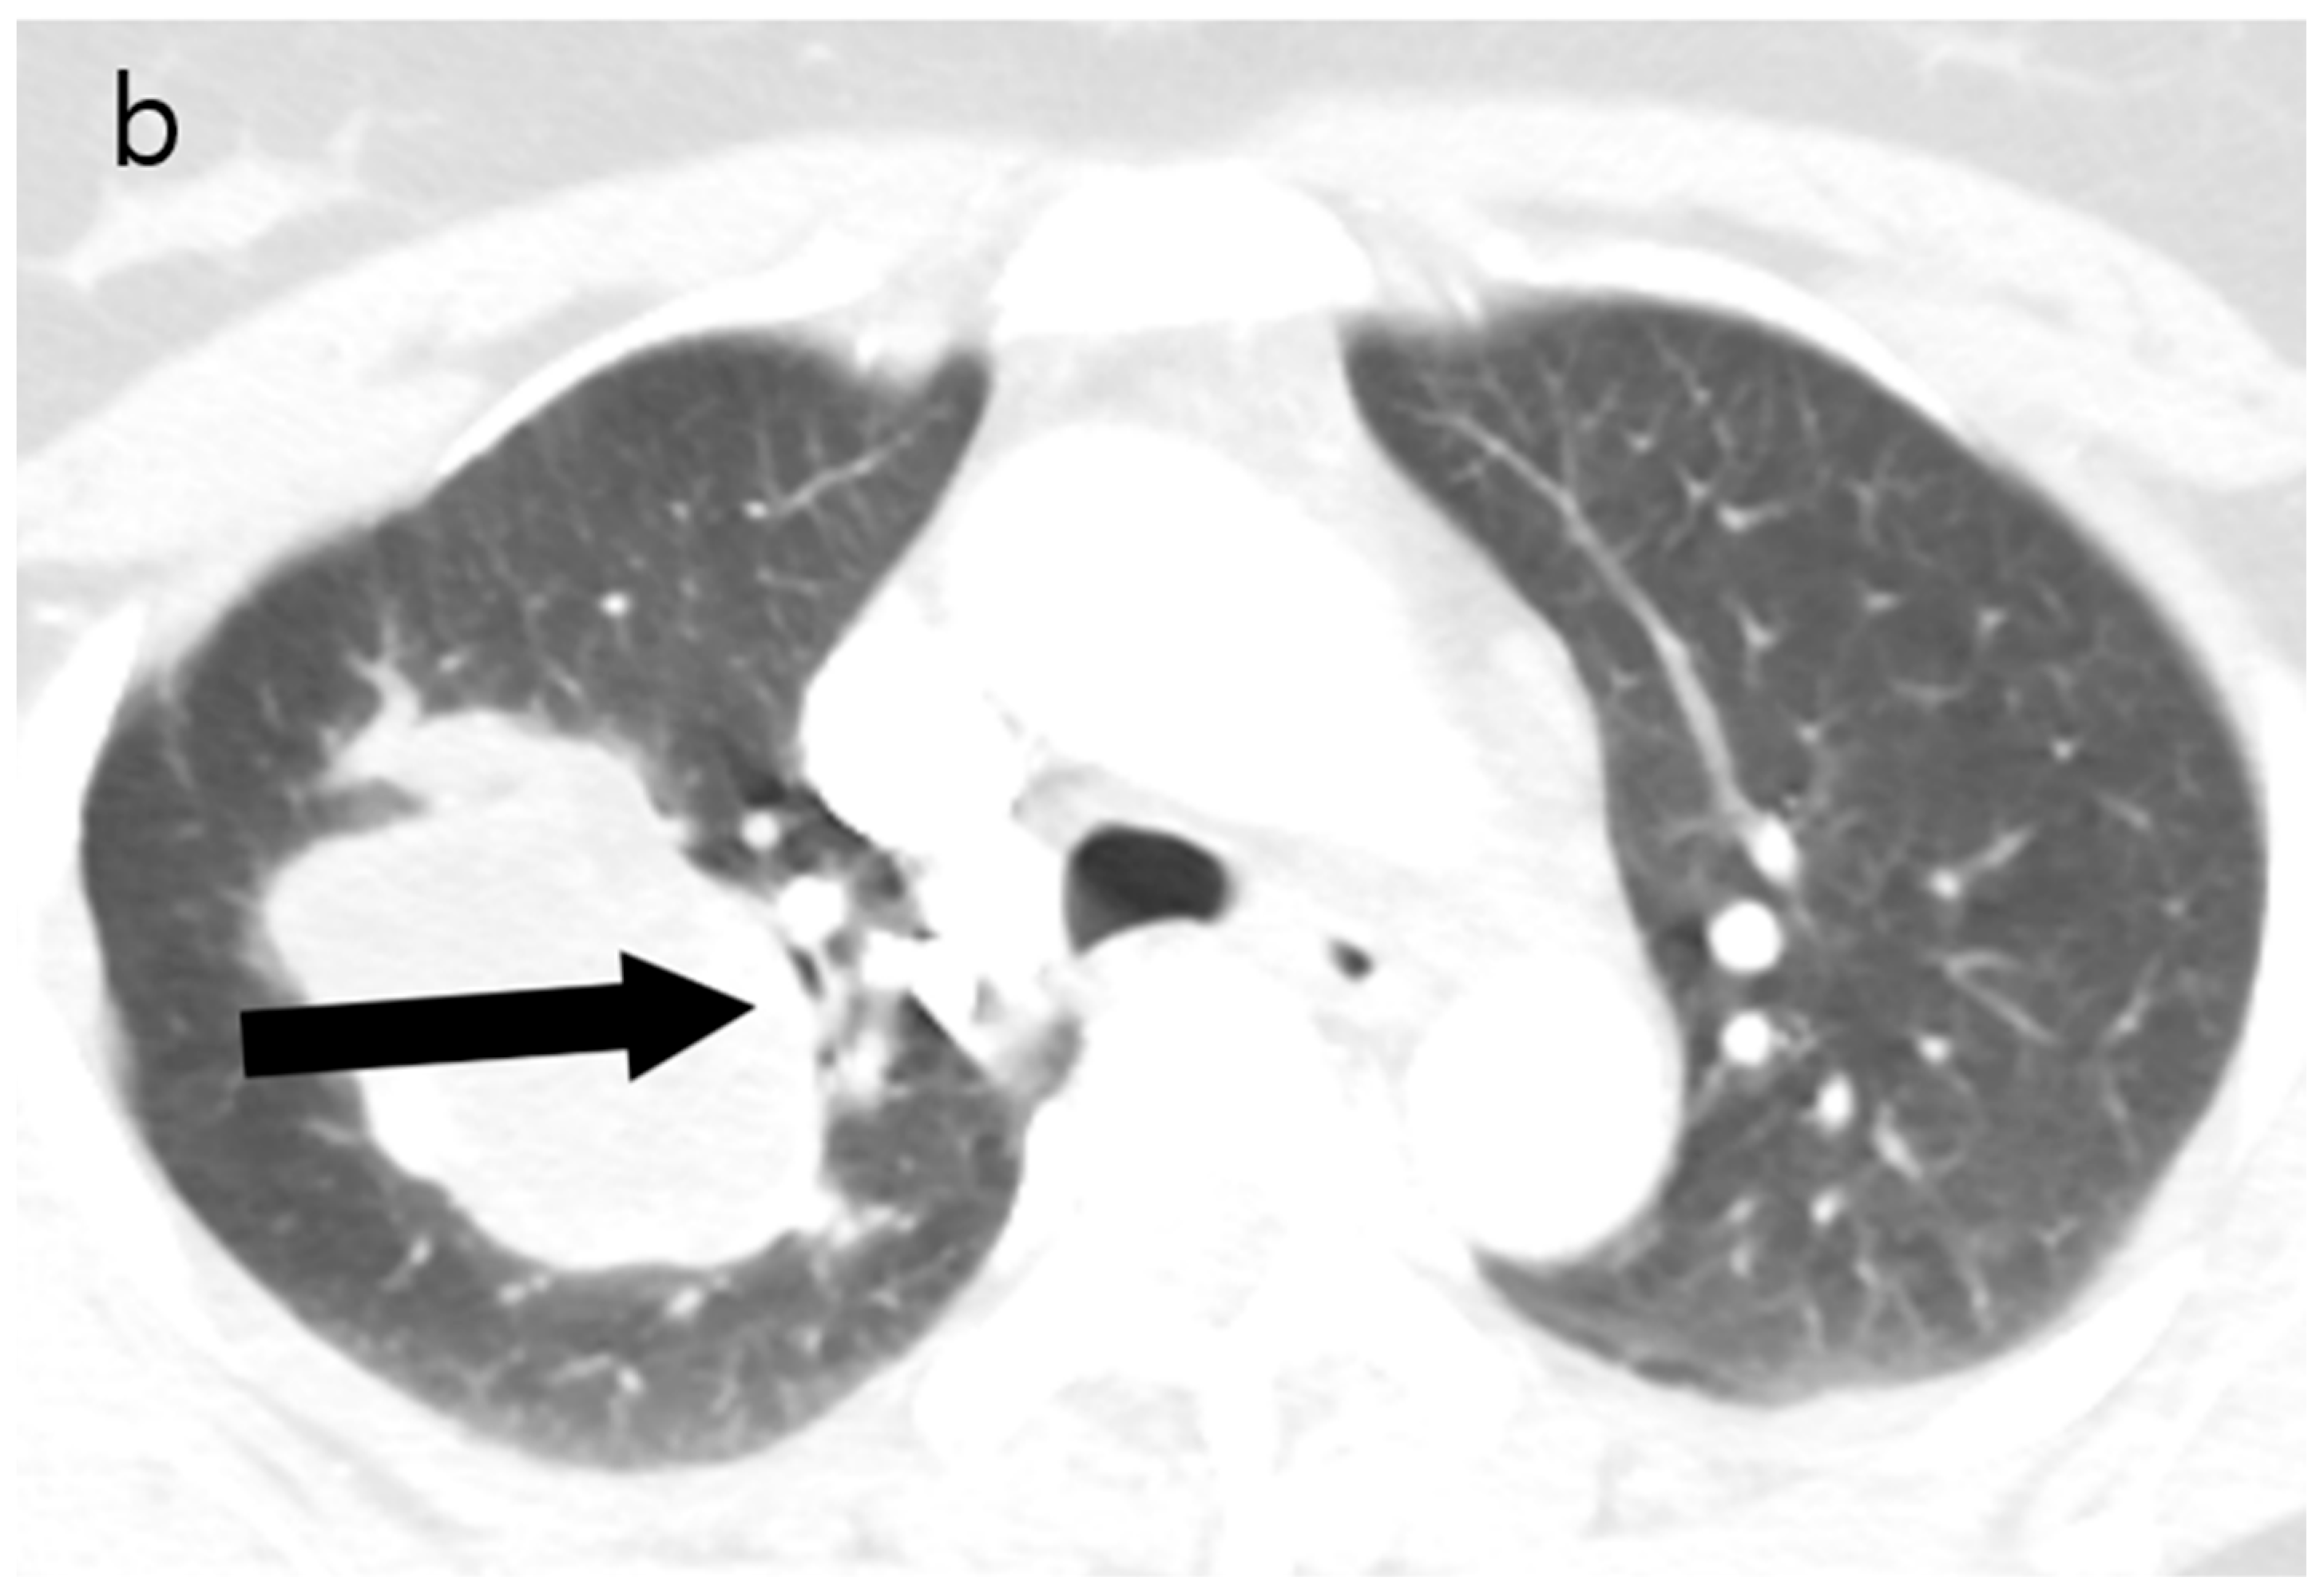

Figure 2.

(a) Unenhanced chest CT showed a homogeneous hypodense mass (5.6 cm in diameter) in the right upper lobe (white arrow). The mass had a well-defined shape with a primarily smooth, but partially beak-like lobulated margin. (b) There was splaying of the anterior and posterior segmental bronchi (black arrow) from the mass effect.